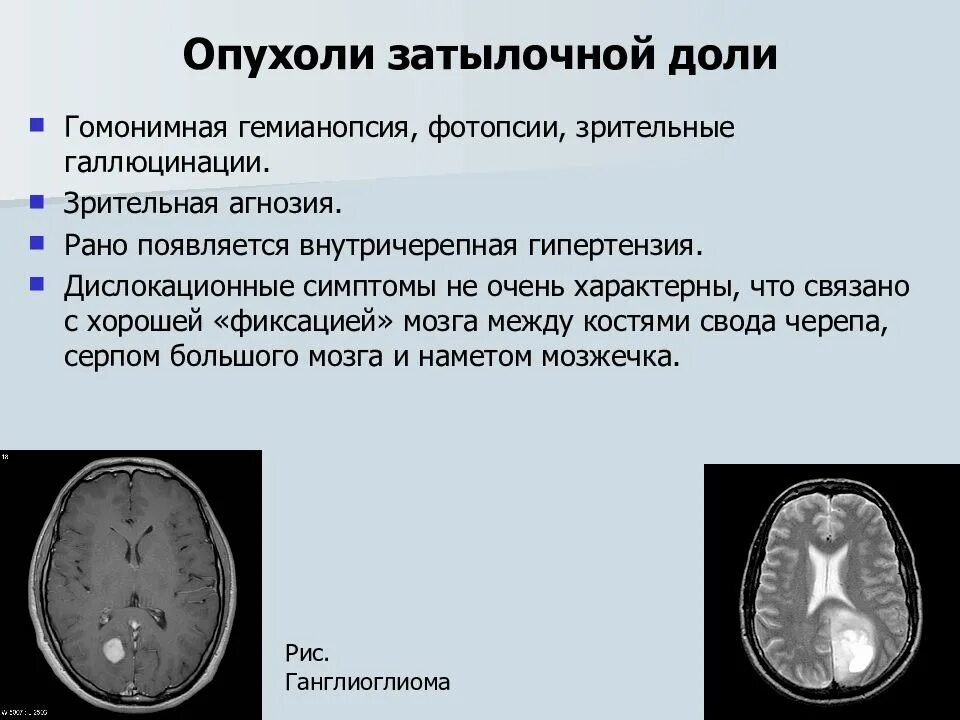

Злокачественные заболевания молочных желез. Новообразование молочной железы. Злокачественная опухоль молочной железы. Доброкачественные новообразования молочной железы. Очаговые симптомы опухоли затылочной доли. Клинические проявления опухоли лобной доли:. Опухоль мозга височной доли симптомы. Опухоль затылочной доли головного мозга.

Очаговые симптомы опухоли затылочной доли. Клинические проявления опухоли лобной доли:. Опухоль мозга височной доли симптомы. Опухоль затылочной доли головного мозга. Гепатомегалия. Симптомы гепатомегалии. Умеренное увеличение печени. Умеренная гепатомегалия.

Фиброаденома молочной железы дифференциальный диагноз. Новообразование молочной железы фиброаденома. Диф диагноз фиброаденомы молочной железы. Фиброаденома молочной железы 30мм-37мм. Диагностические критерии глиомы головного мозга. Особенности опухолей лобной доли. Клиника опухоли затылочной доли головного мозга. Симптомы, характерные для опухолей лобной доли.

Диагностические критерии глиомы головного мозга. Особенности опухолей лобной доли. Клиника опухоли затылочной доли головного мозга. Симптомы, характерные для опухолей лобной доли. Компьютерная томография с болюсным контрастированием. Кт толстой кишки с контрастированием. Кт с болюсным контрастированием что это.